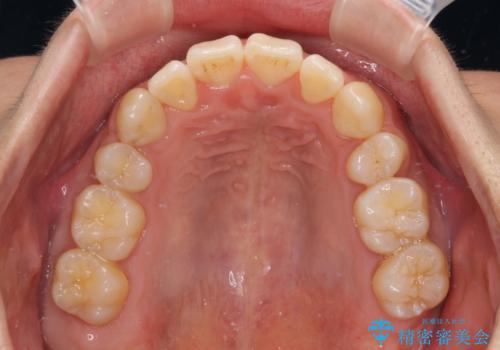

元の歯列が想像できないほど、きれいな歯列に整えることができました。

第二小臼歯抜歯の矯正治療は、治療期間が長引くことが多いですが、動きが非常に良く、予定の治療期間で終えることができました。